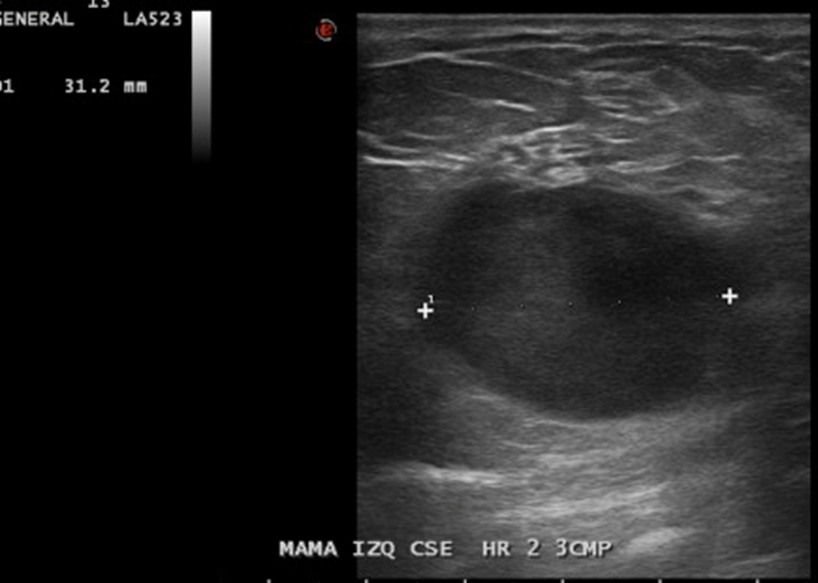

En Mama IZQ CSE HR 2, a 3 CMP, imagen nodular hipoecogénica, ovalada, 31 x 36 x 26 mm.

• La mama izquierda presenta en el cuadrante supero-externo, eje horario 2, a 3 cm. del pezón, imagen nodular hipoecogénica, bien definida, ovalada de 36 x 26 x 31 mm., sugerente de lesión quística con contenido, no vascularizado. Esta lesión presenta escaso refuerzo acústico posterior.

Impresión: Lesión sugerente de quiste con contenido en mama izquierda, se recomienda control evolutivo. BIRADS US 3.